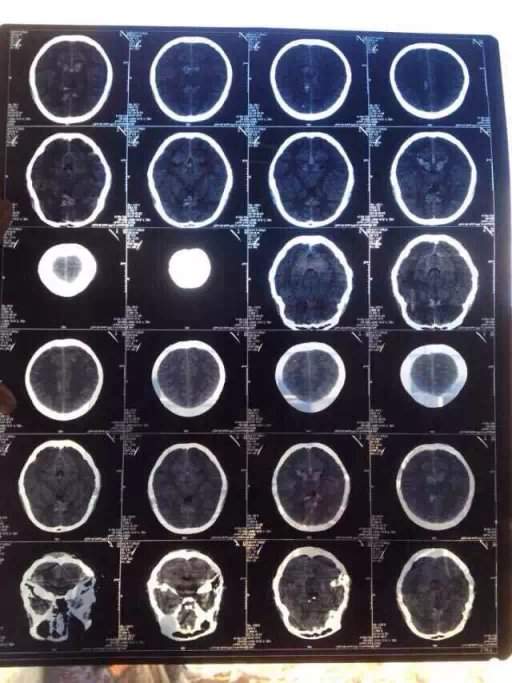

虫友们,帮帮忙,懂的人说说看这是怎么了? 已有6人参与

- 专业: 脑血管结构、功能异常及相